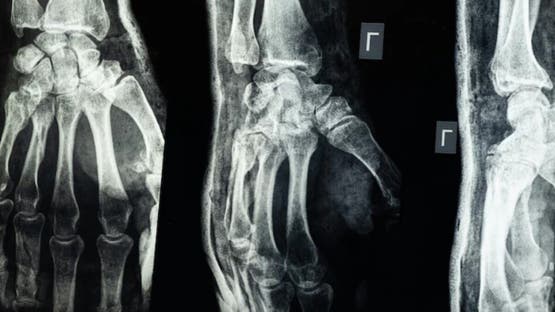

“غراء عظمي”.. ابتكار صيني لعلاج الكسور في 3 دقائق

أعلن فريق بحثي في مقاطعة تشيجيانغ شرق الصين عن ابتكار طبي جديد يتمثل في “غراء عظمي” قادر على معالجة الكسور وتركيب الشظايا العظمية خلال ثلاث دقائق فقط، في خطوة وُصفت بأنها اختراق علمي في عالم جراحة العظام، بحسب ما نقل موقع “إن دي تي في” NDTV.